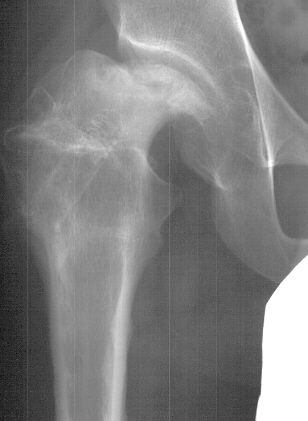

- 2 month Office Follow Up: Rt hip Xray: progressive destruction of capital

femoral epiphysis, cystic changes in metaphysis consistent with AVN.

This case is an example of untreated septic arthritis which caused avascular

necrosis of the proximal femur. The primary cause of this is undrained

septic hip. Repeated aspiration is not adequect treatment of a septic hip.